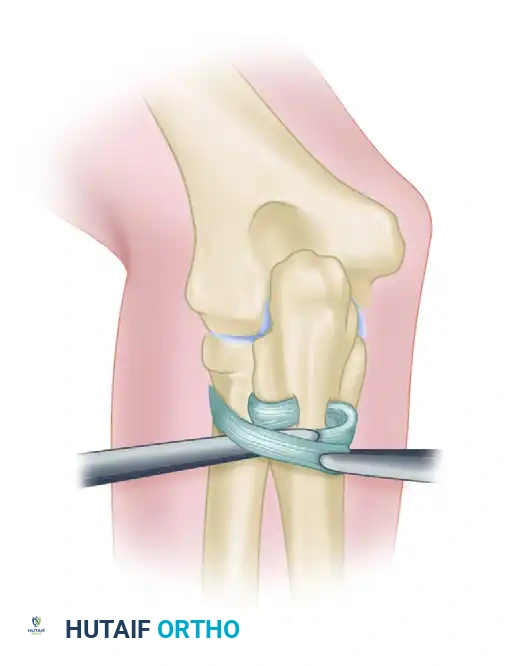

Figure: If primary repair is impossible, the annular ligament can be reconstructed using a strip of fascia lata passed around the radial neck.

- The graft is passed circumferentially around the radial neck and secured to the anterior and posterior margins of the sigmoid notch through drill holes.

- Tensioning must be precise: tight enough to prevent subluxation, but loose enough to permit full, unhindered pronation and supination.

Figure: Completed reconstruction of the annular ligament, restoring proximal radioulnar stability.